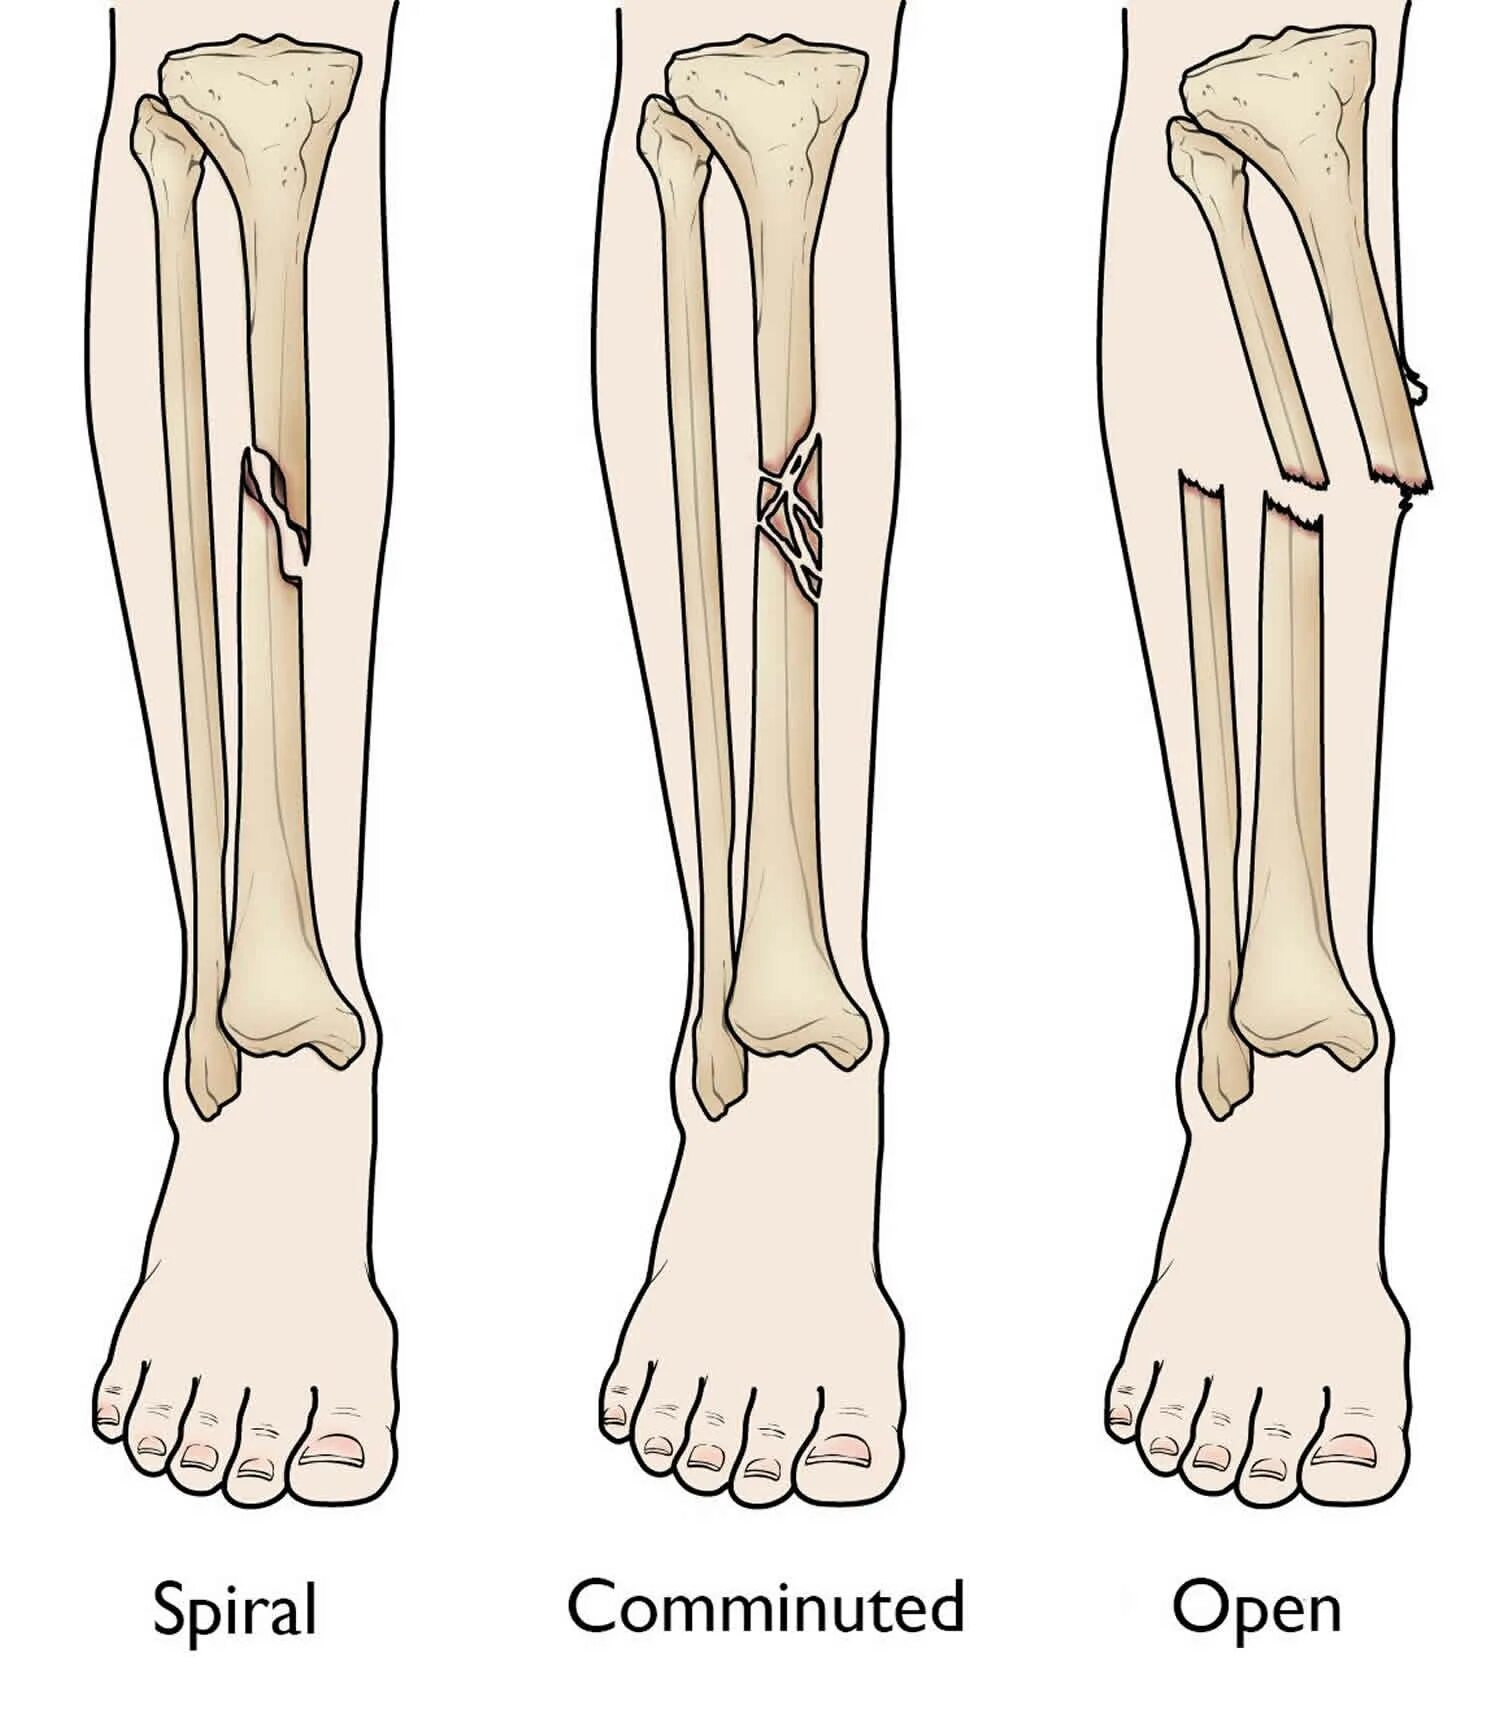

Fracture modeling